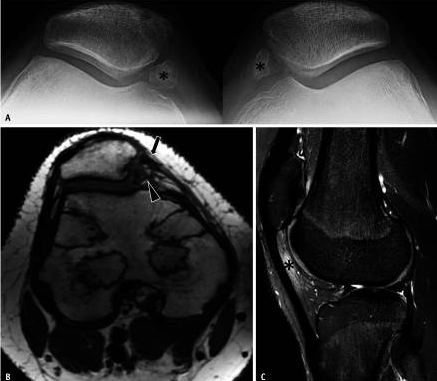

До 70% пациентов будут испытывать рецидивирующий вывих, и может возникнуть хронический рецидивирующий вывих.В этом случае МРТ может показать хронический разрыв медиального стабилизатора, деформацию медиального надколенника, окостенение медиального надколенника, столкновение жира с надколенником и бедренной костью, повреждение хряща и дегенерацию латерального надколенниково-бедренного сустава (рис. 3).